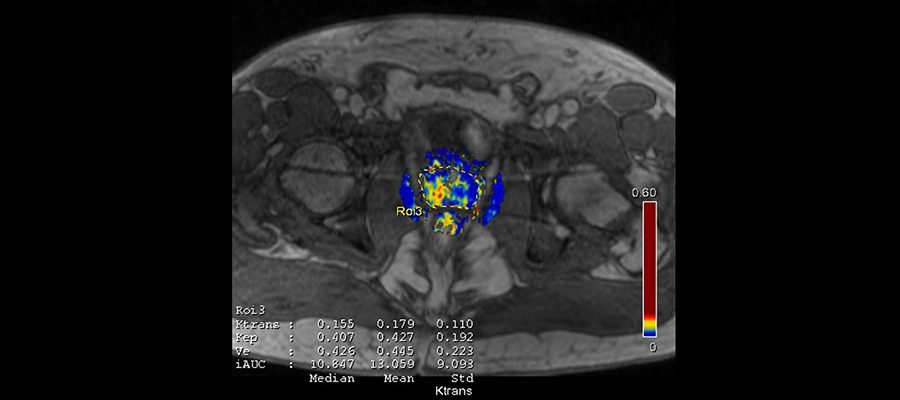

Multiparametrik Prostat Emarı

Prostat kanseri tanısında önemli bir rol oynayan multiparametrik prostat emarı pek çok doktor tarafından talep edilen bir tanı türüdür. Prostat kanserinden şüphelenilen hastaların çoğuna multiparametrik prostat emarı çekimi yapılır.  Bu çekim sayesinde kanser görülen vakalarda erken tanı sağlanır ve hastanın tedavisi hemen başlar.

Prostat kanseri erkeklerde en sık görülen kanser türlerinden bir tanesidir ve ölümcül sonuçlara yol açabilmektedir. Bu hastalık sebebiyle hayatını kaybeden pek çok insanın ölüm sebebi hastalığın farkına çok geç varılmasıdır. Bu sebeple prostatla ilgili sorunlarda erken tanı oldukça önemlidir. Hastalığın tedavisine en kısa sürede başlamak ve hastayı tekrar eski sağlığına kavuşturmak için multiparametrik prostat emarı çekilir. Bu sayede prostat adı verilen bölge detaylı şekilde incelenir ve en erken evredeki kanserlerin bile farkına varılır. Multiparametrik prostat emarı sayesinde pek çok hasta prostat kanserini kısa sürede yenip eski sağlığına kavuşmaktadır. Hastanelerde ve tanı merkezlerinde yapılabilen multiparametrik prostat emarı çekimi manyetik rezonans cihazları kullanılarak yapılır.

Prostat kanseri tanısında kullanılan pek çok yöntem vardır. Bu yöntemler arasında PSA testi, rekatl tuşe, transrektal ultrason eşliğinde biyopsi bulunmaktadır. Sıklıkla kullanılan bu yöntemlerin hastalığı erken evrelerde teşhis etme olasılıkları oldukça düşüktür. Bu sebeple daha etkili bir tanı yöntemi olan multiparametrik prostat emarı çekimi yaptırmak daha doğru olacaktır. Manyetik rezonans cihazları yardımıyla yapılan bu çekim sayesinde prostat bölgesinde meydana gelen herhangi bir sorun rahatlıkla görülebilir. Multiparametrik prostat emarı çektirecek hastaların çoğu bu tanı yöntemi hakkında bilgi sahibi değildir ve çekimin nasıl yapıldığını merak eder.

Multiparametrik prostat emarı  biyopsi işlemi öncesinde yapılır ve biyopsiye öncülük eder.  Prostatı en iyi görüntüleyebilen tanı şekli olan multiparametrik prostat emarı sayesinde kanser teşhisi kısa sürede konulur ve hastanın tedavisine başlanabilir. Multiparametrik prostat emarı çekimi esnasında hastaya koldan ilaç verilir ve çekim bu şekilde gerçekleşir.  Bu ilaç sayesinde prostat çok daha iyi şekilde görülür ve değerlendirilir. Multiparametrik prostat emarı çekilmeden önce kalın bağırsağın boşaltılması gerekir. Bu işlemin amacı prostat bölgesini daha net şekilde görebilmek ve doğru tanı koyabilmektir. Lavman işlemi tamamlandıktan sonra hastaya damar yolu yardımıyla ilaç verilir ve çekime başlanır. Manyetik rezonans cihazı kullanılan bu çekimden önce hasta üzerindeki tüm metallerden kurtulmalıdır.

Multiparametrik prostat emarı son birkaç sene içinde kullanılmaya başlanan önemli bir tanı çeşididir. Bu emar türü yardımıyla prostat bölgesi detaylı bir şekilde görüntülenebilir. Multiparametrik prostat emarı prostat bölgesini en iyi görüntüleyen tanı türü olarak bilinir ve erken tanı konulması için oldukça önemlidir. Biyopsi işlemi öncesinde önemli sonuçlar verip biyopsiye öncülük eden bu çekim yapılmadan önce kalın bağırsağı boşaltmak için lavman yapılır. Daha sonra hastaya damar yolu açılarak ilaç uygulanır. Bu ilacın uygulanmasının sebebi prostat bölgesini çok daha net şekilde görüntüleyebilmektir. Pek çok kişi bu işlemi ürkütücü bulsa da multiparametrik prostat emarı çekimi oldukça acısız ve kolay bir çekimdir. Çekim yapılırken manyetik rezonans cihazları kullanılır ve çekim yaklaşık olarak  30-45 dakika arasında sürer. Multiparametrik prostat emarı çekiminde en büyük amaç  kanser hücresi için erken tanı yapılması ve vakit kaybetmeden tedaviye başlanmasıdır.